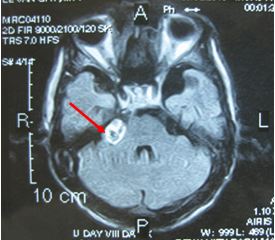

Trước điều trị:  u dây VIII bên phải có kích thước 2cm

Sau xạ phẫu 6 tháng: u nhỏ hơn về kích thước và có hoại tử trong u

Hình 2. Hình ảnh MRI u dây thần kinh số VIII trước và sau xạ phẫu bằng dao gamma quay